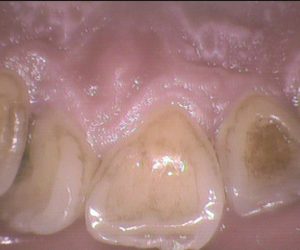

今日のクリーニングです。   初回のクリーニングの後、3ヶ月後にまた来てくださった患者さんです。   クリーニング前(初回)       クリーニング前(3ヶ月後) &n […]